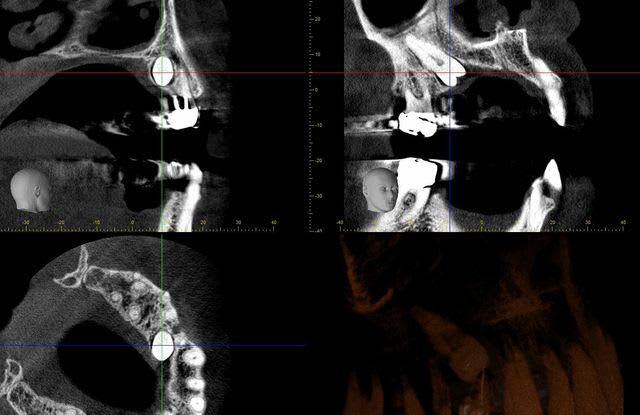

voici 2,3 coupes ...

dans ce cas, c'est différent...le cône beam nous donne toutes les informations nécessaires pour savoir si c'est réalisable ou non, et là oui, pour avoir tracté un certain nombre de dents incluses, il est quasi certain que la mise en place de cette 25 ne posait aucun problème...peut être même en seulement quelques mois...